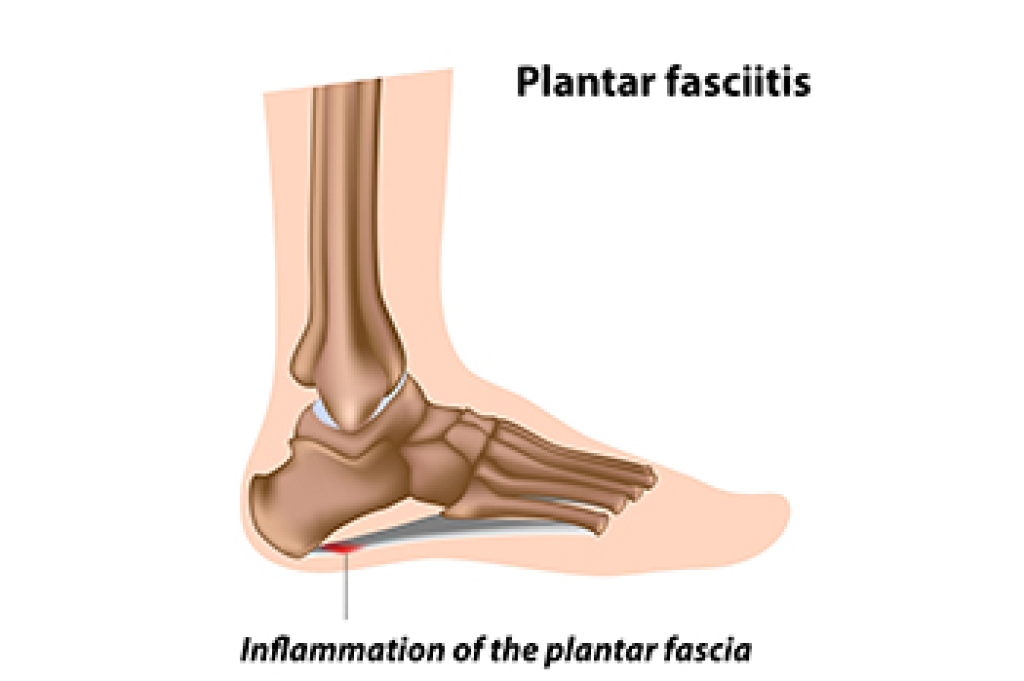

Getting Help for Plantar Fasciitis

Plantar fasciitis is believed to be the most common complaint of heel pain. Plantar fasciitis is the inflammation of the plantar fascia, a broad band of tissue on the sole that supports the arch. This inflammation can make your heel hurt, swell, or turn red, particularly when getting out of bed in the morning. The causes of plantar fasciitis are varied, often stemming from factors like foot and calf tightness, weak foot muscles, or undue stress on the arch. Excessive running, wearing poorly fitted shoes, and some work actions can make the condition worse. Treatment focuses on addressing the root causes and reducing inflammation. It may involve wearing shoes with better arch support, changing shoe size, and moderating activities that strain the foot. Stretching and strengthening exercises, like towel curls, may help reduce symptoms. If you have developed plantar fasciitis, it is suggested that you make an appointment with a podiatrist who specializes in managing this condition.

What Is Plantar Fasciitis?

Plantar fasciitis is the inflammation of the thick band of tissue that runs along the bottom of your foot, known as the plantar fascia, and causes mild to severe heel pain.

What Causes Plantar Fasciitis?

- Excessive running

- Non-supportive shoes

- Overpronation

- Repeated stretching and tearing of the plantar fascia

How Can It Be Treated?

- Conservative measures – anti-inflammatories, ice packs, stretching exercises, physical therapy, orthotic devices

- Shockwave therapy – sound waves are sent to the affected area to facilitate healing and are usually used for chronic cases of plantar fasciitis

- Surgery – usually only used as a last resort when all else fails. The plantar fascia can be surgically detached from the heel

While very treatable, plantar fasciitis is definitely not something that should be ignored. Especially in severe cases, speaking to your doctor right away is highly recommended to avoid complications and severe heel pain. Your podiatrist can work with you to provide the appropriate treatment options tailored to your condition.